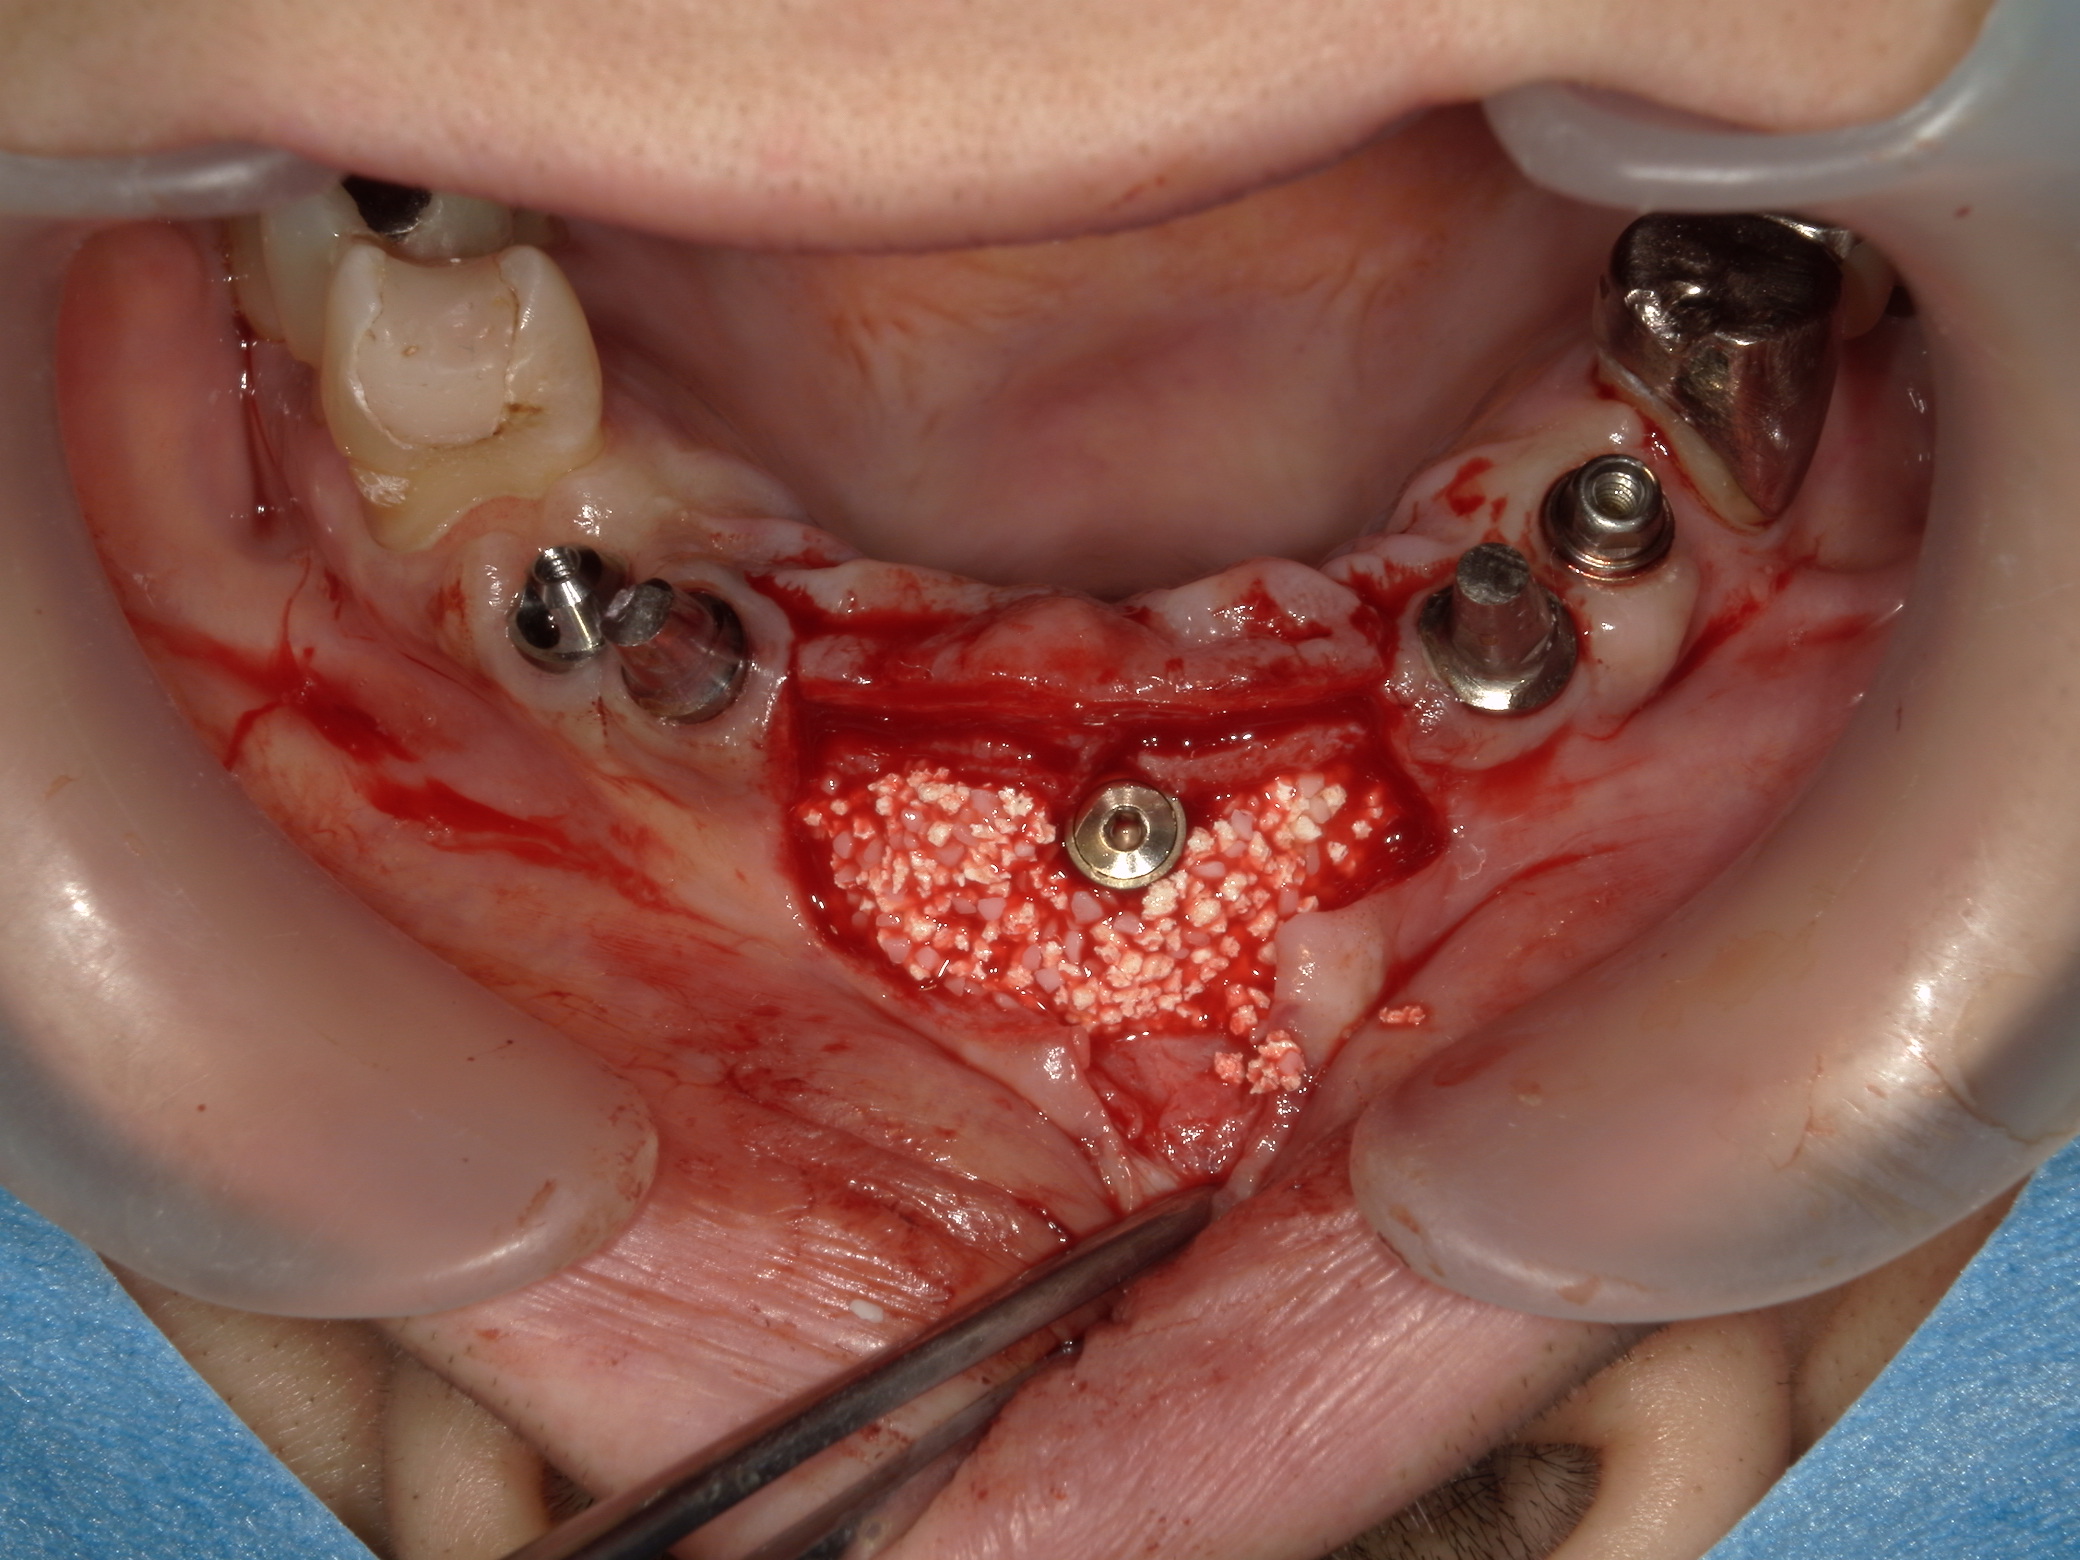

上の写真は上顎右側1番にインプラントを埋入し同時に骨造成を行ったところです。人工骨はβ-tcp(アローボーン)とHA(ボーンタイト)を3対2で混合したものを使用しています。人工骨はAFGと混合しゲル状に固めたものを皮質骨を穿孔させ出血させ、その上に置きました。

インプラント 骨造成 骨が足りない 能代市、北秋田市、秋田市、大館市

剥離反転させた歯肉弁には骨膜減張切開を加え縫合は水平マットレス方向と単純縫合を組み合わせています。骨造成の際は人工骨に加わるマイクロムーブメントの防止を徹底させる必要があります。その為には暫間補綴物が大切で暫間補綴物と歯肉の間に食物残渣が入らないようにし更に暫間補綴物が脱落しないようにします。